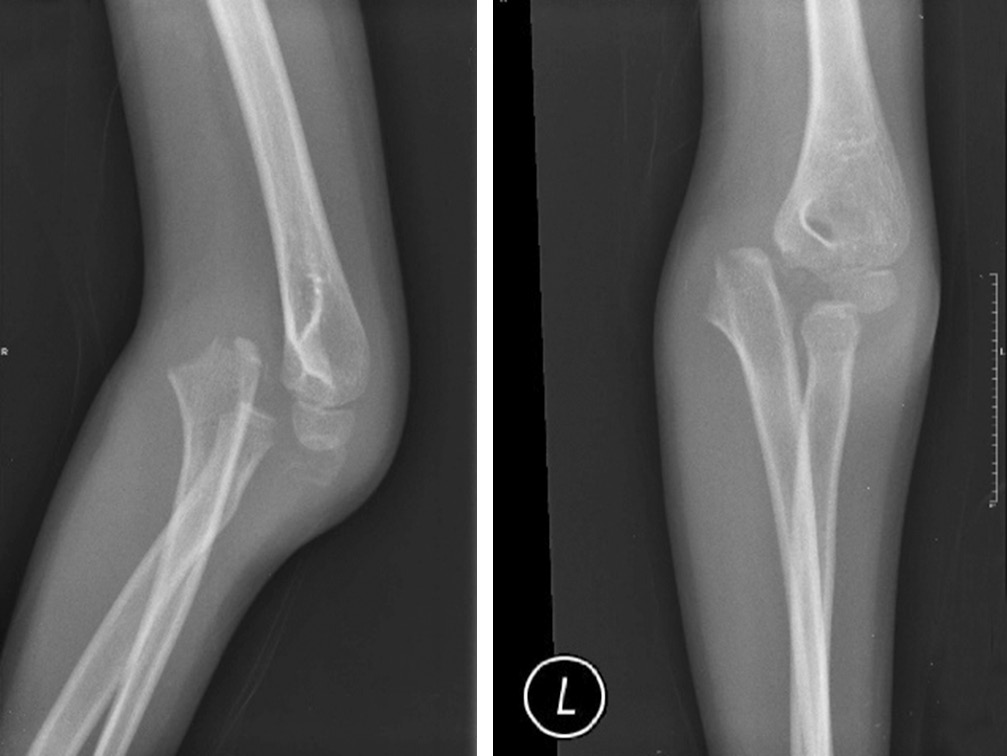

На обзорной рентгенограмме левого локтевого сустава выявлен передний вывих с переломом локтевого отростка (рис. 1). Примерно через два часа после травмы в отделении скорой помощи была предпринята попытка закрытого ручного устранения вывиха, которая оказалась неуспешной. Приблизительно через 6 ч после травмы под общей анестезией выполнено открытое устранение вывиха с чрескожной фиксацией спицей Киршнера. Для ревизии локтевого нерва и репозиции перелома выбран медиальный доступ. Интраоперационно обнаружено ущемление локтевого нерва дистальным фрагментом локтевой кости несколько дистальнее борозды медиального мыщелка. Нерв был натянут, его цвет казался слегка бледным, но целостность была не нарушена. Лучевой нерв был мобилизован проксимально и дистально до исчезновения натяжения. Перелом локтевого отростка произошел в области метафиза, при этом отломок кости был прикреплен в метаэпифизарной зоне, что соответствовало перелому II типа по Salter-Harris. Для репозиции выполнена осторожная контролируемая тракция за локоть. Перелом фиксирован двумя параллельными спицами Киршнера, репозиция головки лучевой кости была спонтанной. Полностью разорванная медиальная коллатеральная связка была восстановлена с помощью рассасывающейся нити 5/0. Интраоперационно оценена стабильность: локтевой сустав был стабилен в супинации, пронации, сгибании и разгибании. После репозиции и восстановления мягких тканей определялась хорошая пульсация на плечевой, лучевой и локтевой артериях. С помощью лонгеты локтевой сустав иммобилизован под углом 90° с предплечьем в положении супинации (рис. 2).

Рис. 2. Обзорная рентгенограмма левого локтевого сустава после операции. Вывих устранен, для стабилизации перелома локтевого отростка установлены спицы Киршнера